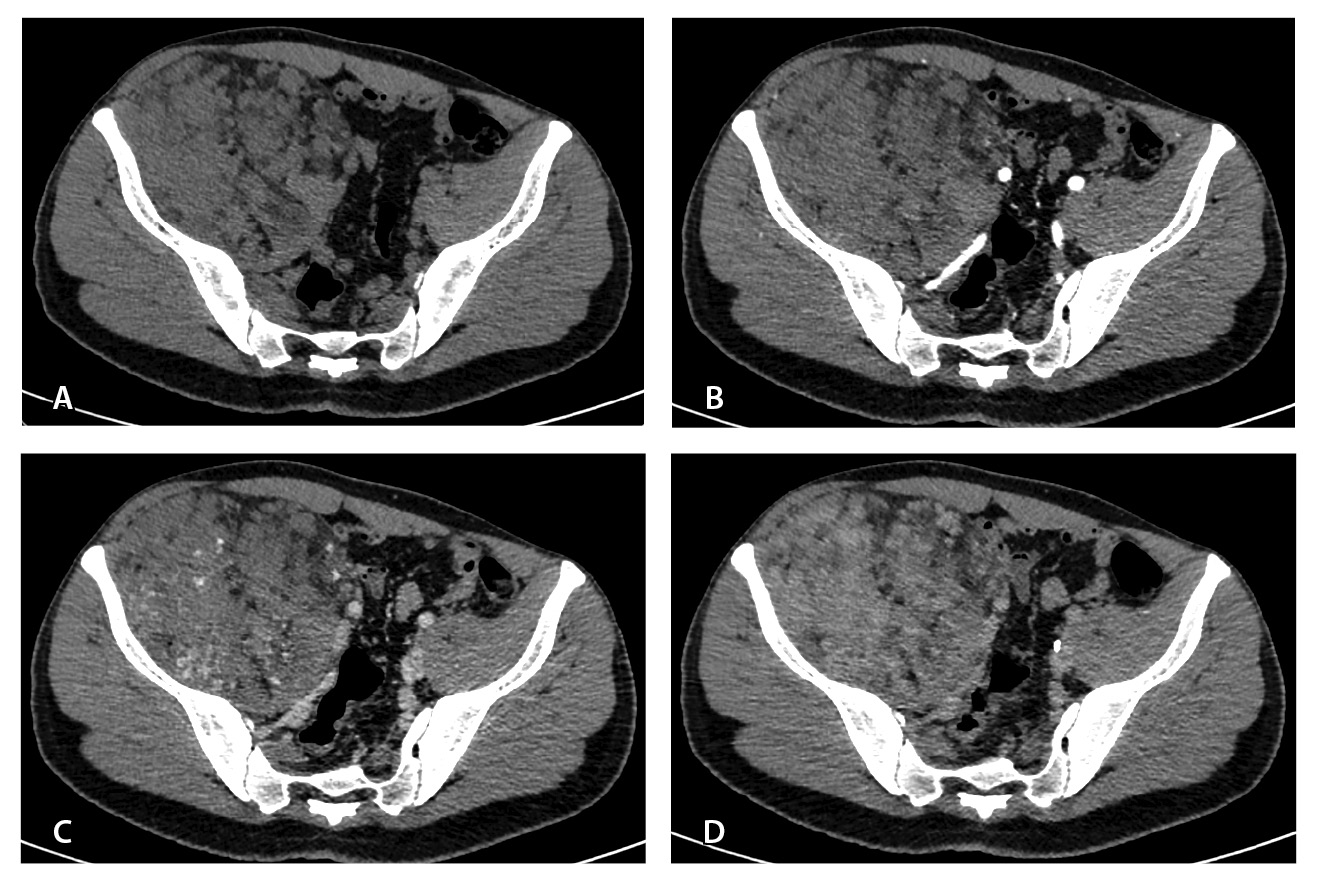

Результаты дооперационной мультиспиральной компьютерной томографии органов брюшной полости и забрюшинного пространства (рис. 1, 2): «В забрюшинном пространстве справа визуализируется образование, исходящее из подвздошно-поясничной мышцы, с выходом вдоль сосудистого пучка на верхнюю треть бедра. Образование с четкими и ровными контурами, размерами 145 × 125 × 125 мм. Структура образования гетерогенная, плотность в нативную фазу исследования от –40 до 50 HU, содержит единичные кальцинаты, жировую ткань и мягкотканный компонент. На фоне контрастирования в артериальную и венозную фазы в структуре выявляются извитой формы участки гиперконтрастирования (сосудистая сеть). Максимальное накопление контрастного препарата происходит преимущественно к отсроченной фазе исследования. Усредненные плотностные характеристики составляют 25, 36, 53 и 59 HU в нативную, артериальную, венозную и отсроченную фазы соответственно. Опухоль оттесняет тазовую брюшину, правую подвздошно-поясничную мышцу, илеоцекальный угол кпереди. Образование тесно прилежит сзади к крылу правой подвздошной кости и лобковой кости, спереди – к прямой и внутренней косым мышцам живота, верхним контуром – к поясничной мышце. Медиально в средней трети по контуру образования проходят правые наружные и внутренние подвздошные сосуды, со сдавлением наружной подвздошной вены. Данных за распространение на прилежащие внутренние органы и клетчатку не получено. Кости без деструктивных изменений».

Рис. 1. Мультиспиральная компьютерная томография органов брюшной полости и забрюшинного пространства с болюсным внутривенным контрастированием: А – нативная фаза, Б – артериальная фаза, В – венозная фаза, Г – отсроченная фаза. Крупное гетерогенной структуры образование забрюшинного пространства справа, с фокусами гиперваскуляризации в структуре. Тесно прилежит к крылу подвздошной кости и подвздошным сосудам, оттесняя последние медиально